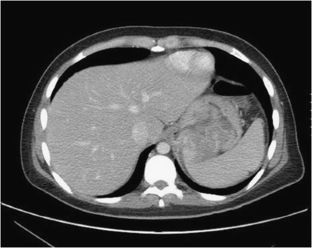

Fig. 2